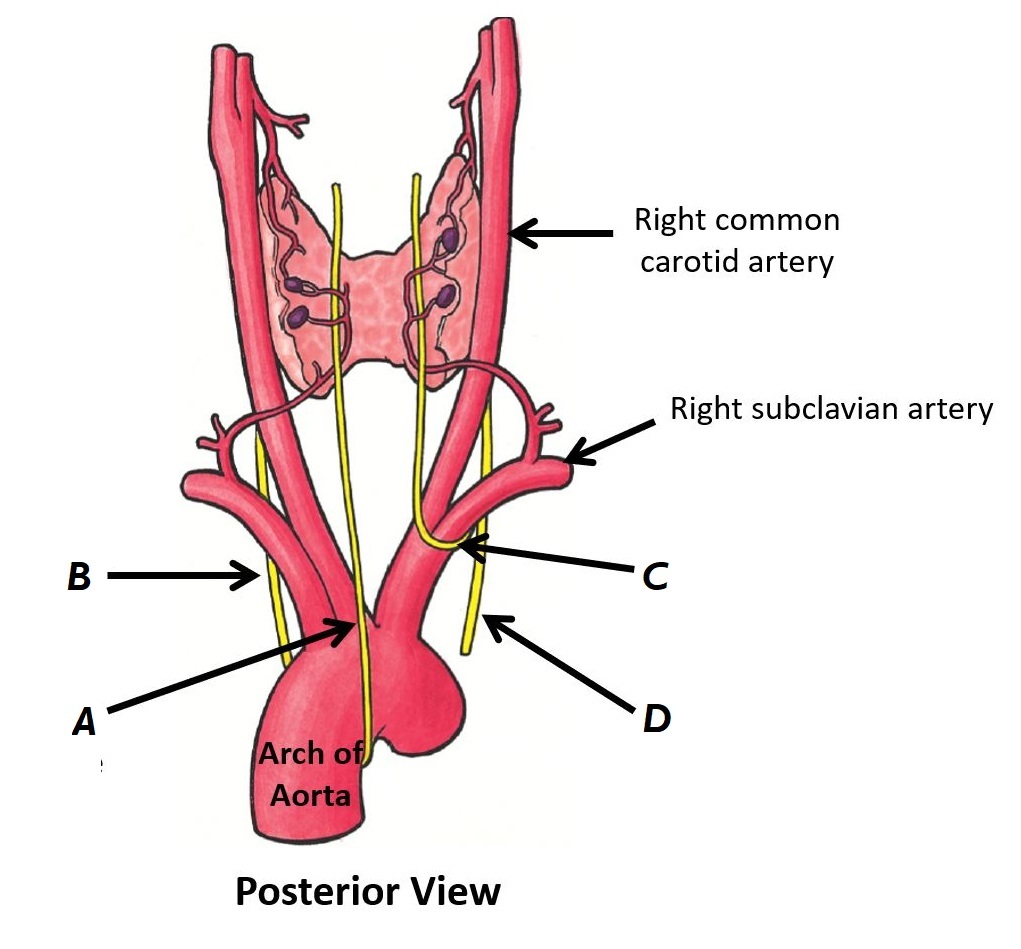

Name nerves A to D

A - Left recurrent laryngeal nerve

B - Left vagus nerve

C - Right recurrent laryngeal nerve

D - Right vagus nerve

Name structures A and B

A - Right vagus nerve

B - Right subclavian artery